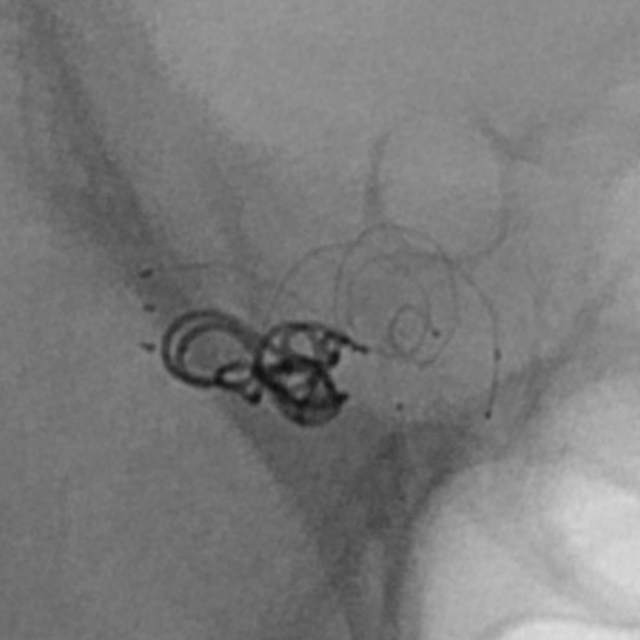

手术过程:术中采用“一个支架+一个弹簧圈”的简约模式顺利结束手术,消除了动脉瘤破裂出血的风险。

手术结果:本次手术具有“创伤小、花费少、时间短、出院快”的特点,而且支架紧邻分叉部近段,没有覆盖大脑前动脉、支架打开贴壁良好、所有分支保持通畅~~~